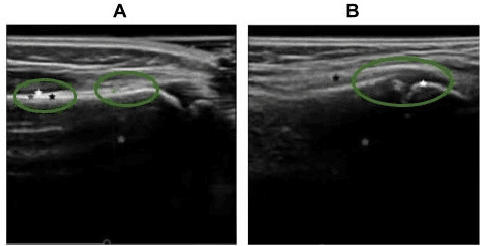

Abstract:Most applications of deep learning techniques in medical imaging are supervised and require a large number of labeled data which is expensive and requires many hours of careful annotation by experts. In this paper, we propose an unsupervised, physics driven domain specific transporter framework with an attention mechanism to identify relevant key points with applications in ultrasound imaging. The proposed framework identifies key points that provide a concise geometric representation highlighting regions with high structural variation in ultrasound videos. We incorporate physics driven domain specific information as a feature probability map and use the radon transform to highlight features in specific orientations. The proposed framework has been trained on130 Lung ultrasound (LUS) videos and 113 Wrist ultrasound (WUS) videos and validated on 100 Lung ultrasound (LUS) videos and 58 Wrist ultrasound (WUS) videos acquired from multiple centers across the globe. Images from both datasets were independently assessed by experts to identify clinically relevant features such as A-lines, B-lines and pleura from LUS and radial metaphysis, radial epiphysis and carpal bones from WUS videos. The key points detected from both datasets showed high sensitivity (LUS = 99\% , WUS = 74\%) in detecting the image landmarks identified by experts. Also, on employing for classification of the given lung image into normal and abnormal classes, the proposed approach, even with no prior training, achieved an average accuracy of 97\% and an average F1-score of 95\% respectively on the task of co-classification with 3 fold cross-validation. With the purely unsupervised nature of the proposed approach, we expect the key point detection approach to increase the applicability of ultrasound in various examination performed in emergency and point of care.

Abstract:Ultrasound examination for detecting fractures is ideally suited for Emergency Departments (ED) as it is relatively fast, safe (from ionizing radiation), has dynamic imaging capability and is easily portable. High interobserver variability in manual assessment of ultrasound scans has piqued research interest in automatic assessment techniques using Deep Learning (DL). Most DL techniques are supervised and are trained on large numbers of labeled data which is expensive and requires many hours of careful annotation by experts. In this paper, we propose an unsupervised, domain specific transporter framework to identify relevant keypoints from wrist ultrasound scans. Our framework provides a concise geometric representation highlighting regions with high structural variation in a 3D ultrasound (3DUS) sequence. We also incorporate domain specific information represented by instantaneous local phase (LP) which detects bone features from 3DUS. We validate the technique on 3DUS videos obtained from 30 subjects. Each ultrasound scan was independently assessed by three readers to identify fractures along with the corresponding x-ray. Saliency of keypoints detected in the image\ are compared against manual assessment based on distance from relevant features.The transporter neural network was able to accurately detect 180 out of 250 bone regions sampled from wrist ultrasound videos. We expect this technique to increase the applicability of ultrasound in fracture detection.